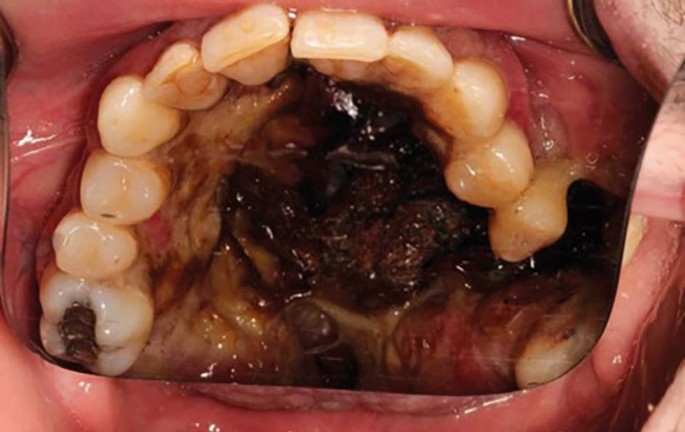

CIMDL with extensive oral and nasopharyngeal destruction

On examination, there was a loss of the nasal columella and saddle nose deformity. Intra-orally, there was complete erosion of the hard and soft palate and destruction of the nasal septum, with superimposed overgrowth of tissue and suppuration extending from the anterior hard palate posteriorly toward the oropharynx. The defect was surrounded with florid angiomatous tissue and bordered with crusted necrotic tissue (Fig. 5, Fig. 6). All remaining maxillary teeth were mobile (Fig. 7).